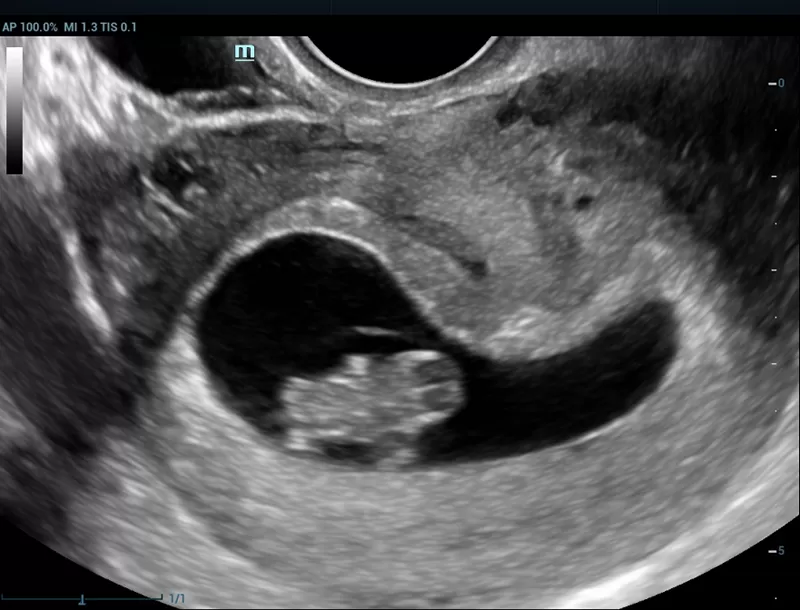

We will be at your disposal with our well trained partners, who will present the outstanding characteristics of the Resona premium ultrasound a truly revolutionary platform with ten times faster scanning speed due to its unique zone sonography technology ZST+

The Resona series, stands out not only for its cutting edge imaging technology but also for its flexible analysis tools offering high display quality and increased diagnostic precision.

- Smart face